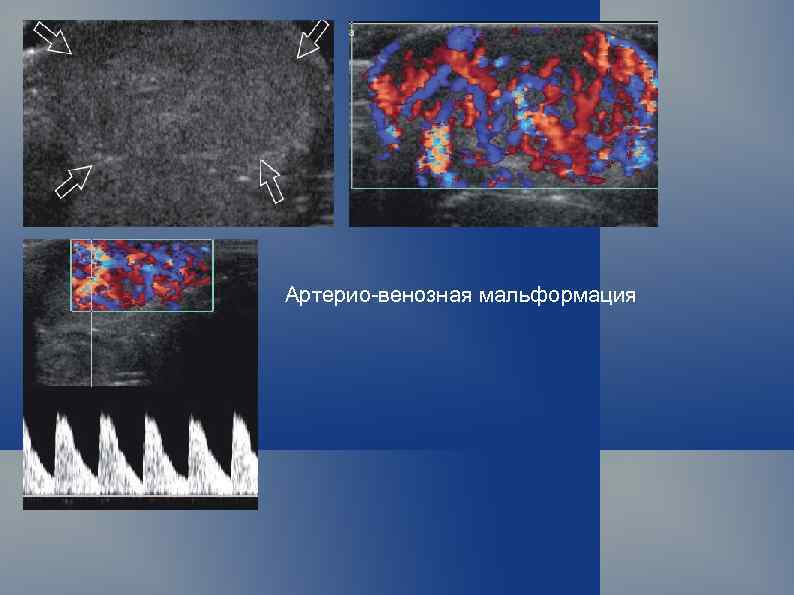

Артерио-венозная мальформация

Артерио-венозные мальформации и гемангиомы мягких тканей Первые упоминания, касающиеся артериовенозных соустий сосудов конечностей, относятся к XVIII в. , когда в 1737 г. появились публикации В. Hunter, описавшего артериовенозные фистулы. Одной из первых фундаментальных работ по врожденной сосудистой патологии является монография Trelat и Movod (1869), в которой авторы пришли к выводу, что заболевание, характеризующееся гипертрофией конечностей, варикозным расширением подкожных вен и капилляров, возникает вследствие врожденного нарушения развития сосудов.

Турбулентный высокоскоростной поток в зоне ангиоматоза.